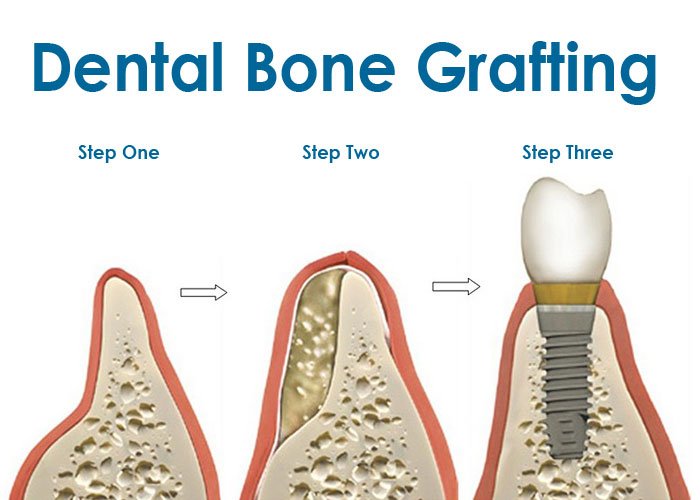

Bone grafting can repair implant sites with inadequate bone structure due to previous extractions, gum disease, or injuries. The bone is either obtained from a tissue bank or your own bone is taken from the jaw, hip or tibia (below the knee). Sinus bone grafts are also performed to replace bone in the posterior upper jaw. In addition, special membranes may be utilized that dissolve under the gum to protect the bone graft, as well as encourage bone regeneration. This is called guided bone regeneration, or guided tissue regeneration.

With bone grafting we now have the opportunity to not only replace bone where it is missing, but we also have the ability to promote new bone growth in that location. This not only gives us the opportunity to place implants of proper length and width, it also gives us a chance to restore functionality and aesthetic appearance.

A ridge augmentation is a common dental procedure often performed following a tooth extraction. This procedure helps recreate the natural contour of the gums and jaw that may have been lost due to bone loss from a tooth extraction, or for another reason.

The alveolar ridge of the jaw is the bone that surrounds the roots of teeth. When a tooth is removed an empty socket is left in the alveolar ridge bone. Usually this empty socket will heal on its own, filling with bone and tissue. Sometimes when a tooth is removed the bone surrounding the socket breaks and is unable to heal on its own. The previous height and width of the socket will continue to deteriorate.

The key to a successful and long-lasting dental implant is the quality and quantity of jaw bone to which the implant will be attached. If bone loss has occurred due to injury or periodontal disease, a sinus augmentation can raise the sinus floor and allow for new bone formation. A sinus lift is one of the most common bone grafting procedures for patients with bone loss in the upper jaw. The procedure seeks to grow bone in the floor of the maxillary sinus above the bony ridge of the gum line that anchors the teeth in the upper jaw. This enables dental implants to be placed and secured in the new bone growth.